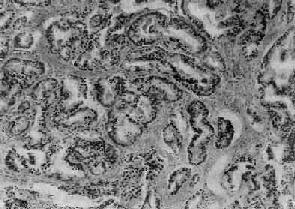

镜下,97%的前列腺癌均为腺癌,少数为移行细胞癌和鳞状细胞癌。依其分化程度可分为高分化、中分化和低分化3型。高分化前列腺癌最多见,癌细胞排列成大小不等的腺样结构,颇似前列腺增生腺体,但癌细胞体积较小,核较深染,上皮细胞往往呈多层排列并较不规则(图14-4),有时可呈乳头状腺癌或腺泡腺癌结构,并常可见癌组织向间质浸润生长;中分化腺癌全部或部分呈腺样结构,但腺体排列较紊乱,核异型性较明显,且有时形成筛状结构;低分化腺癌的癌细胞一般较小,排列成实体团块或条索,腺腔样结构很少(图14-5)。多数病例乃由上述多种组织结构混合组成。

图14-4 前列腺癌(高分化型)

腺体密集,癌细胞体积较小,核深染,上皮细胞呈多层排列并较不规则,可见间质浸润